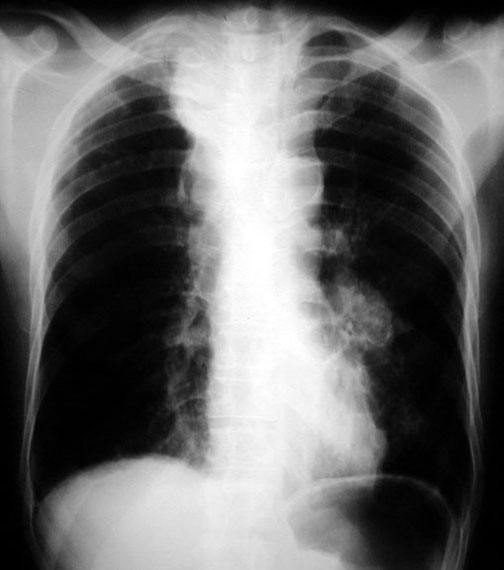

Air Fluid Level

• In mediastinum in PA view (not seen clearly)

• Lung cancer with esophageal obstruction

• Loculated effusion

• Paratracheal mass

• Left hilar mass